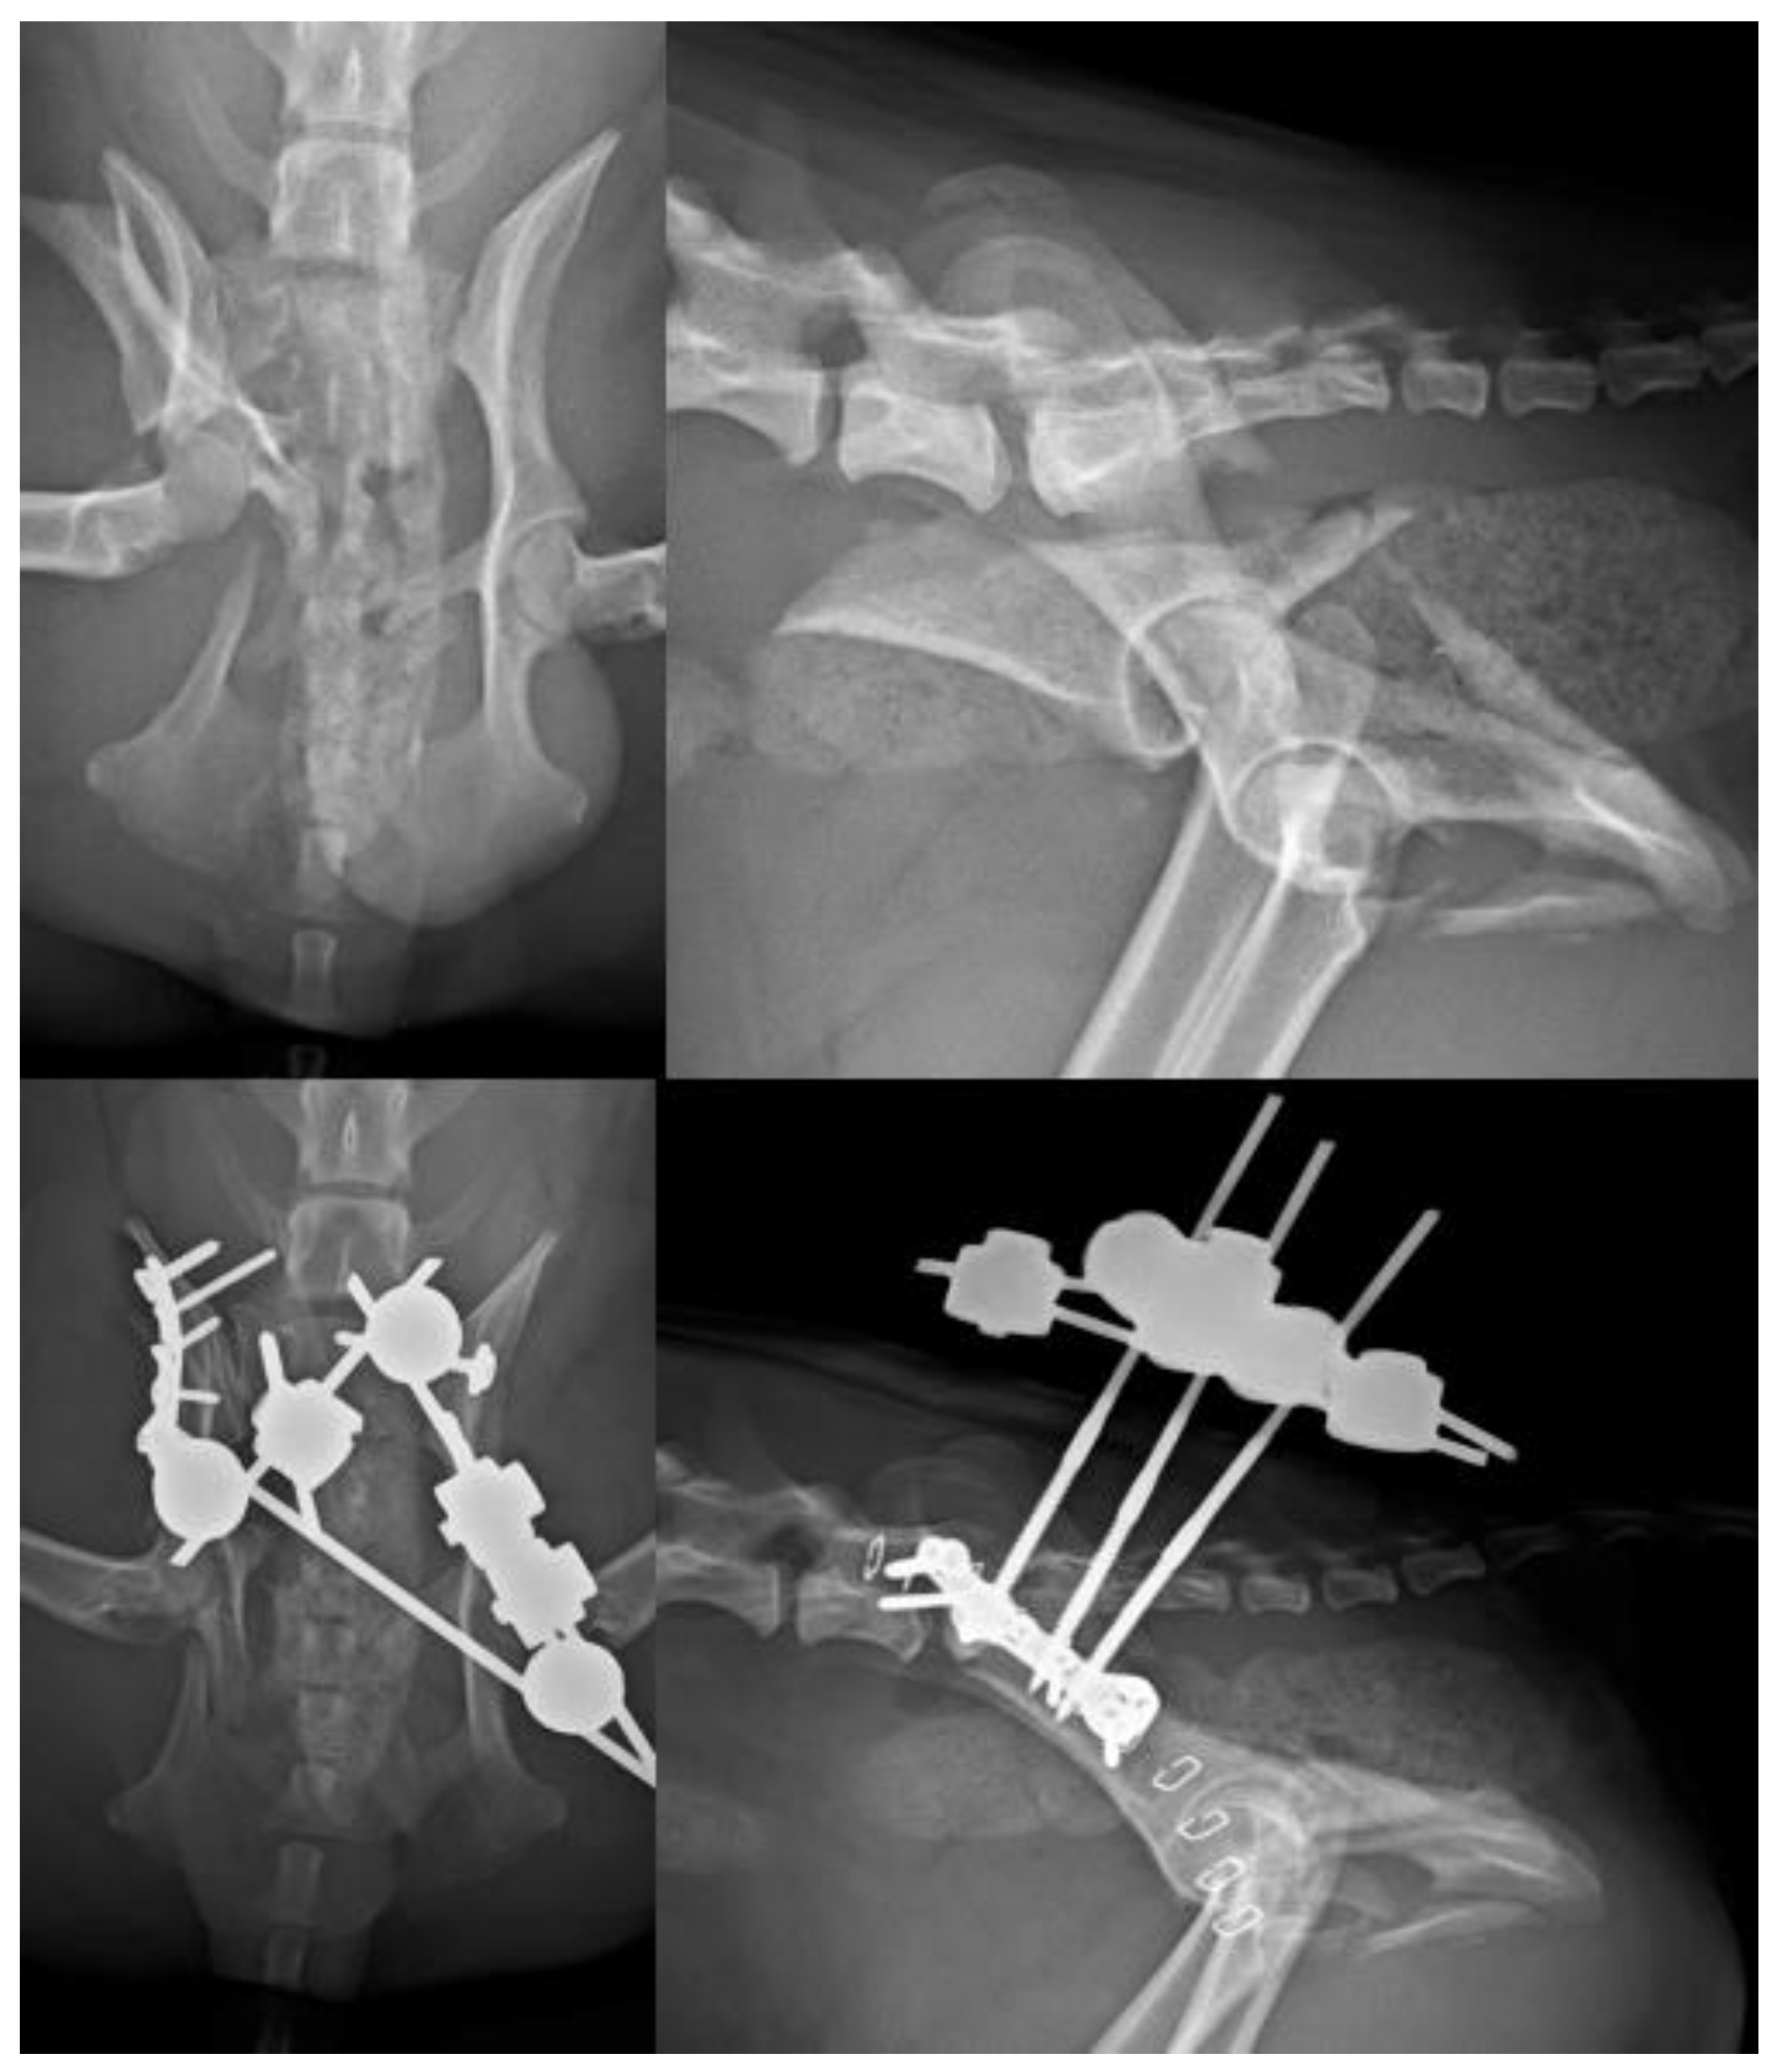

Figure 9. (Left): Radiograph of a patient treated with a type X EF. Note the fracture located on the ischial branch of both hemipelves and the pins inserted into the 7th lumbar vertebra to stabilize an additional fracture of the right sacral articular process. (Right): Picture of the external appearance of the EF.